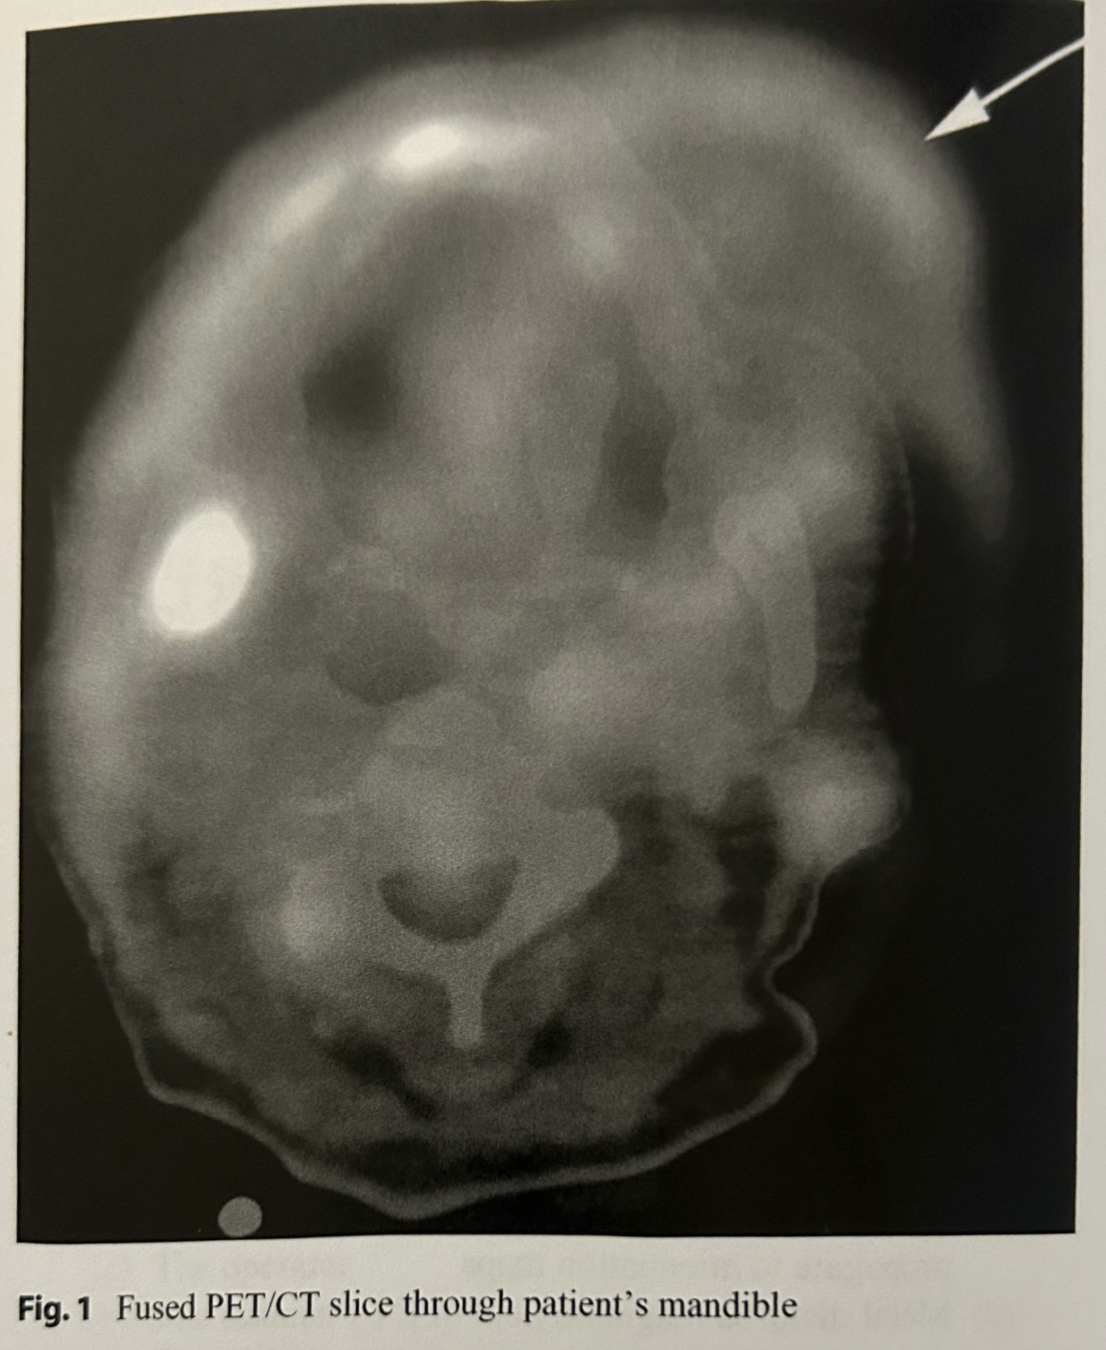

Refer to Fig. 1. In this fused PET/CT transaxial slice through the mandible, what is the likeliest explanation for the area of activity extending outside the boundary of the CT (see arrow)?

Patient tilted head between CT and PET